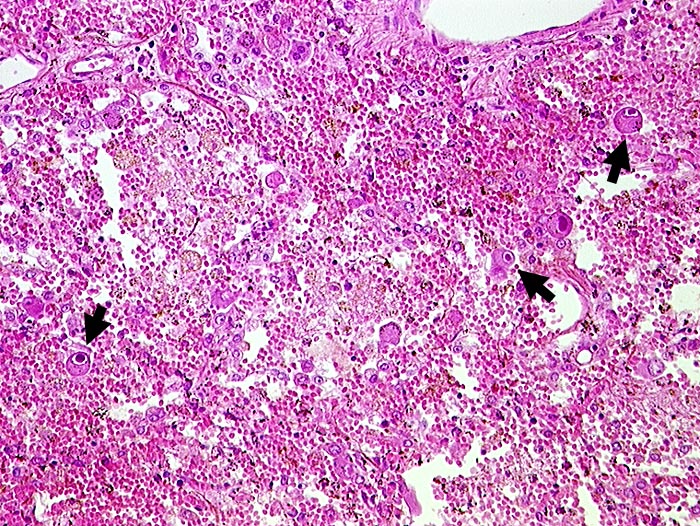

Das Zytomegalievirus befällt Makrophagen und Endothelzellen von immunsupprimierten Patienten. Die virusbefallenen Zellen sind deutlich vergrössert und enthalten einen grossen intranukleären Einschlusskörper, der sich durch einen schmalen hellen Zytoplasmasaum von der Kernmembran abhebt (Eulenaugenzellen). Die bis zu 1 Mikrometer grossen zytoplasmatischen Einschlusskörper konzentrieren sich meist im paranukleären Zytoplasma. Der Ausstrichhintergrund in der BAL ist oft sauber, da aufgrund der Immunsuppression eine entzündliche Reaktion fehlt.